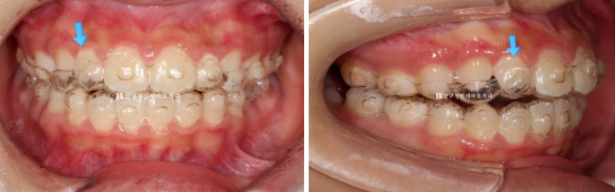

24.11

파란 화살표 측절치 배열이 잡히지 않아 들려있고 아랫니와 절단교합을 보이면서 이러한 교합간섭 때문에 중심선이 약간 틀어진 모습입니다.

인비절라인 장치를 껴보면 파란 화살표 측절치가 장치와 떠 있는 것이 보입니다.

장치 끼는 시작이 부족하여 인비절라인 장치가 치아를 잡아주지 못하고 놓쳐버린 것 입니다.

출국일이 두달 후로 임박했고 인비절라인 장치를 재제작할 시간은 없었습니다.

위 앞니 6개에 MTA 장치를 붙이고 중절치와 측절치 높이를 맞추는 과정을 한달간 거쳤습니다.